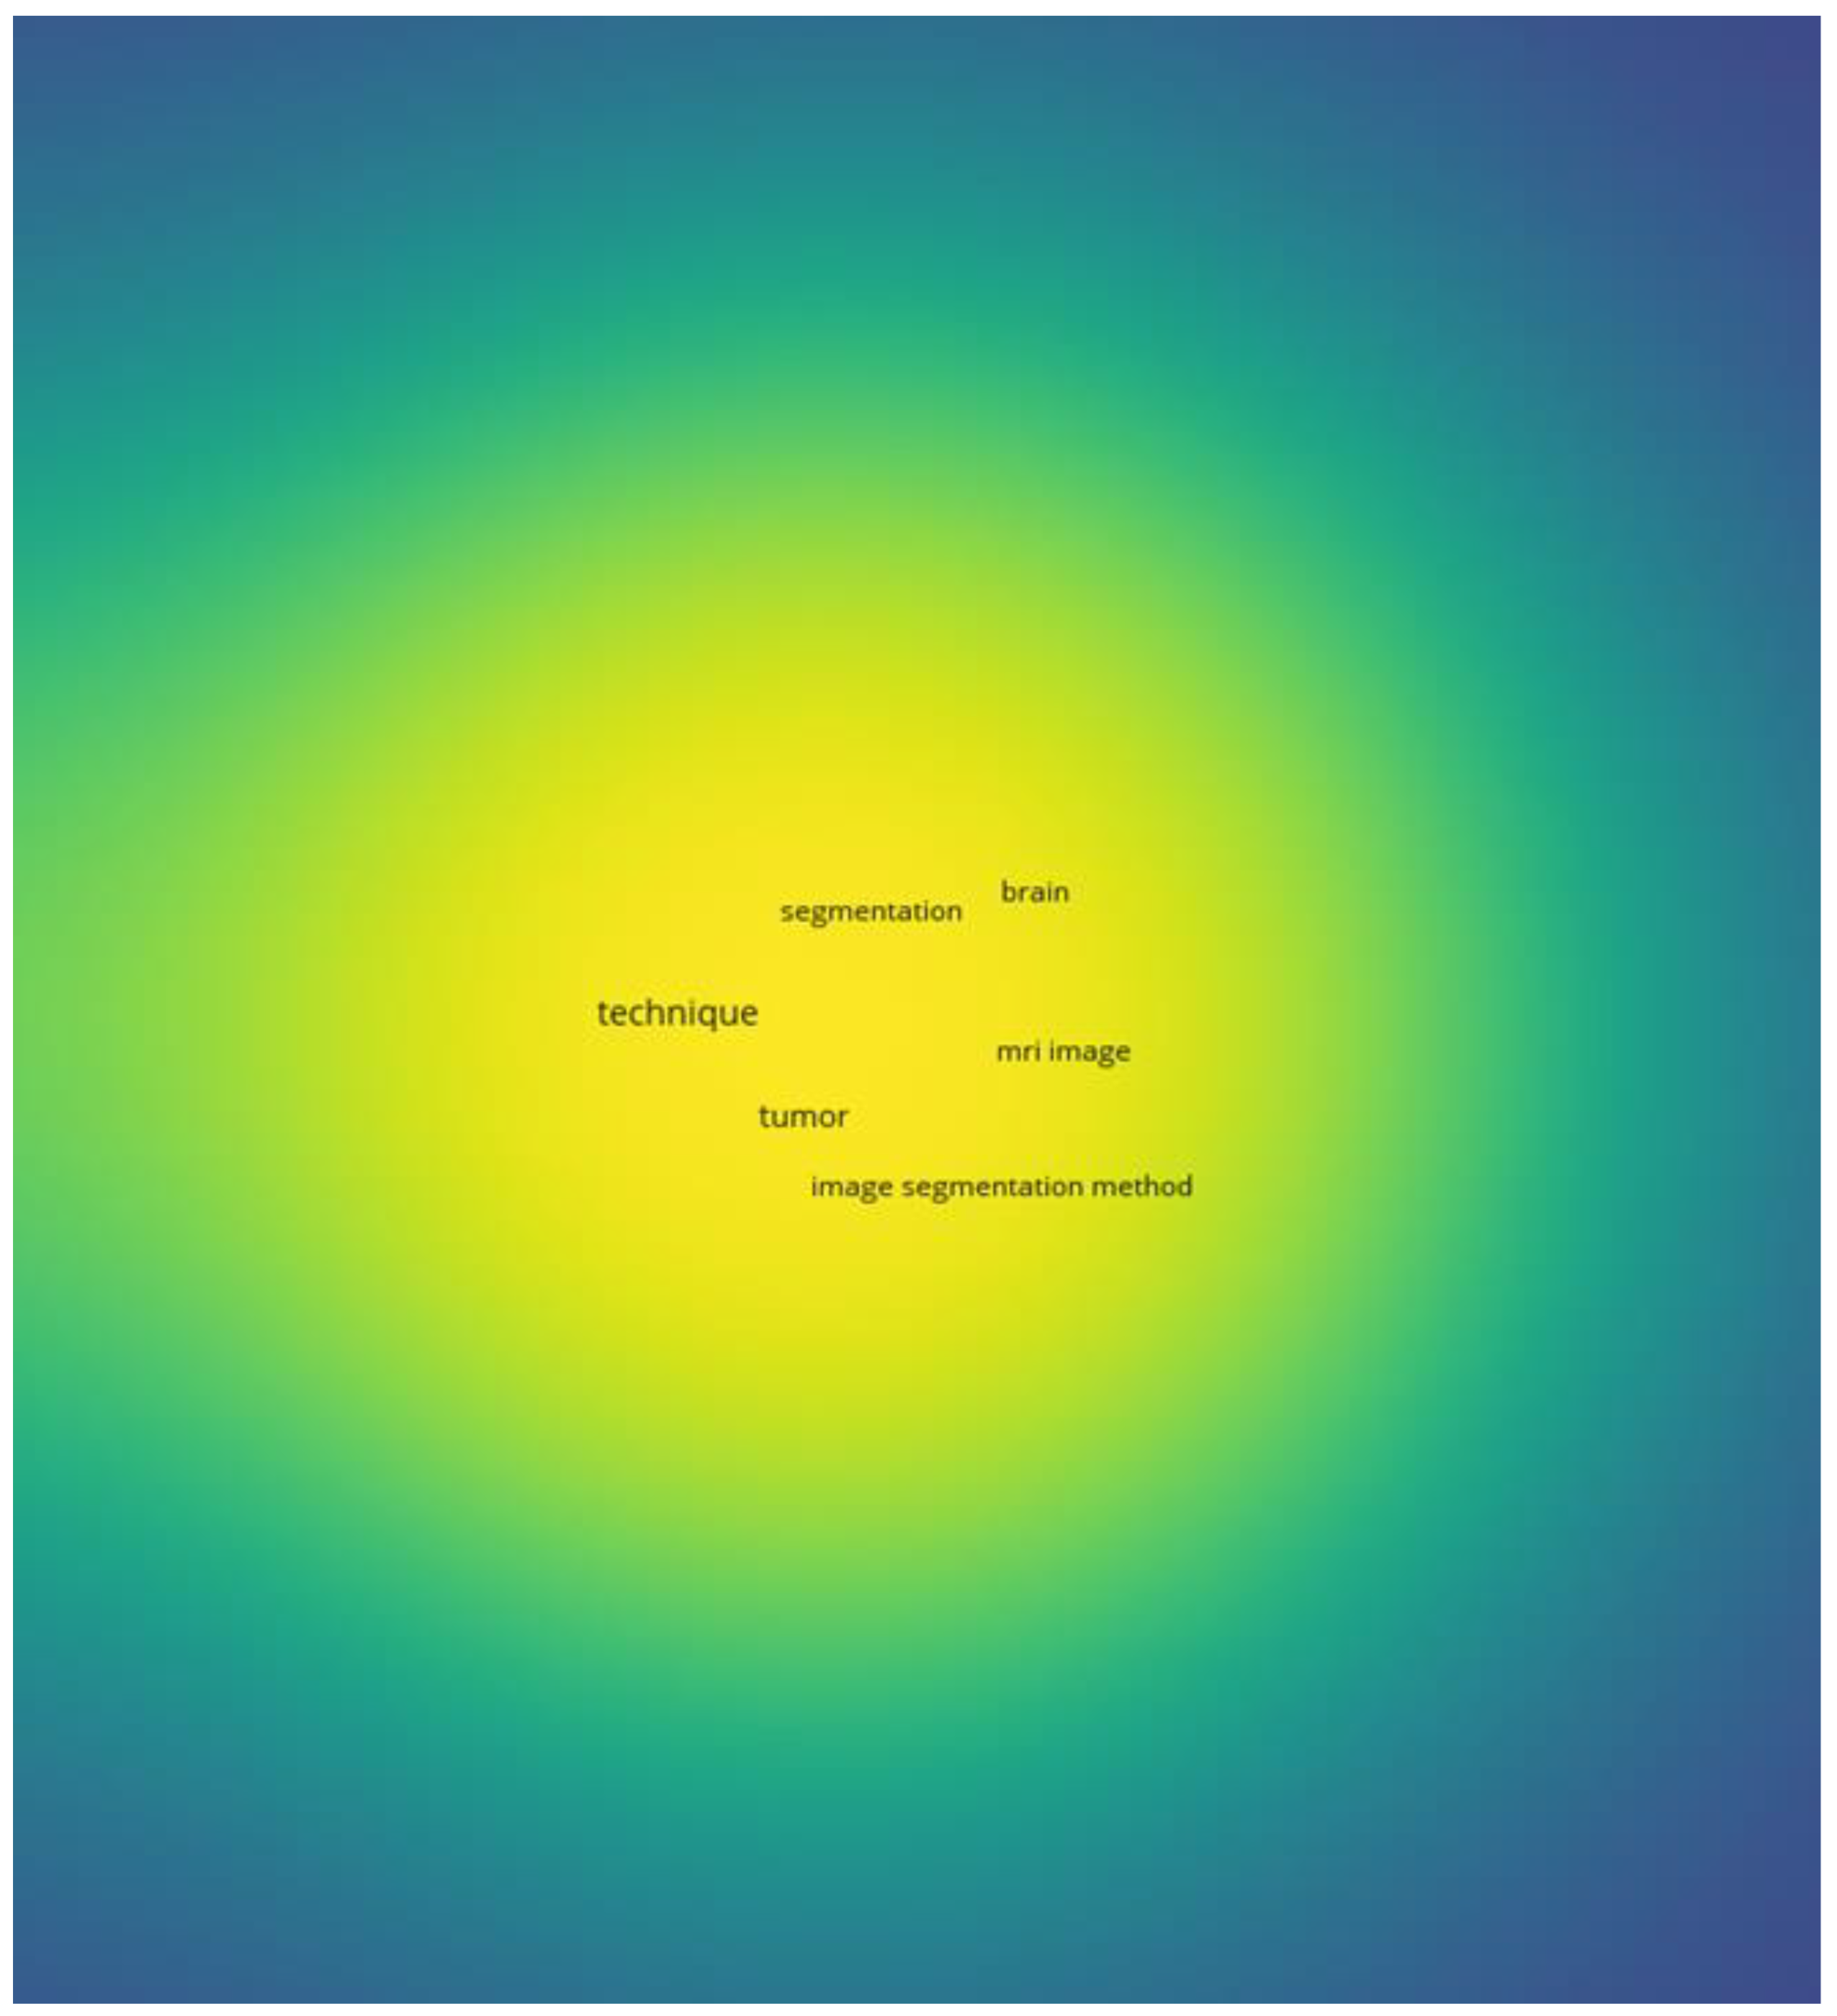

3.6. AI and Machine Learning in Disease Diagnosis